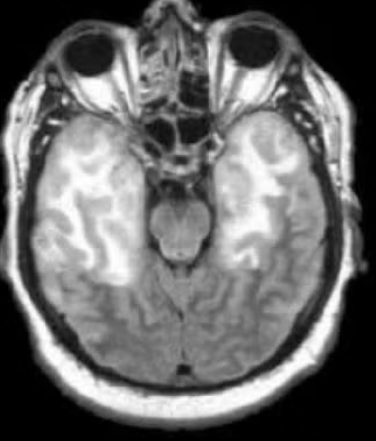

CASO 2

Uomo di 41 anni, febbre da 3 giorni, confusione, crisi epilettica focale.

Qual è la diagnosi più probabile?

Risposta esatta: C

Il coinvolgimento dei lobi temporali mesiali, spesso asimmetrico, con possibile componente emorragica è altamente suggestivo per encefalite da HSV-1.

Il punto fine:

- Distribuzione limbica

- Tendenza a coinvolgere corteccia e sostanza bianca subcorticale

- Possibili microemorragie

L’infarto arterioso non rispetterebbe questa distribuzione.

Il glioma non evolve così rapidamente né con febbre.